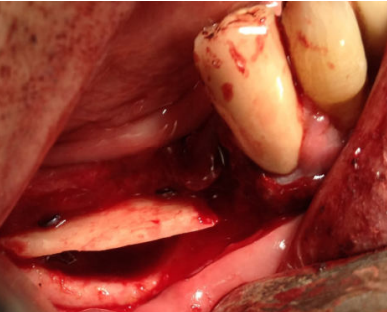

Se planificó la realización de la técnica de Khoury bajo anestesia local y sedación consciente intravenosa. Se realizó una incisión en mucosa libre extendiéndose desde el trígono retromolar hasta el canino homolateral (Figura 3). El colgajo resultante permitió el acceso para la obtención de un injerto en bloque de unos 3 mm de espesor procedente de la línea oblicua externa mandibular del cuadrante homolateral, mediante instrumental piezoeléctrico. La región del trígono retromolar y de la rama ascendente se utilizó para obtener hueso autógeno particulado mediante el uso de un rascador.